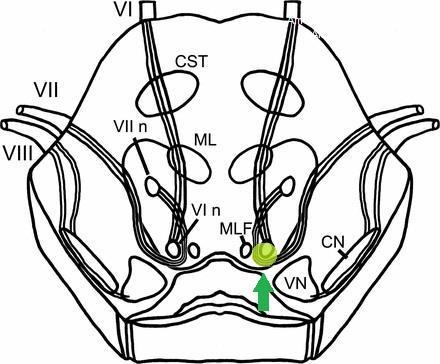

Facial colliculus syndrome